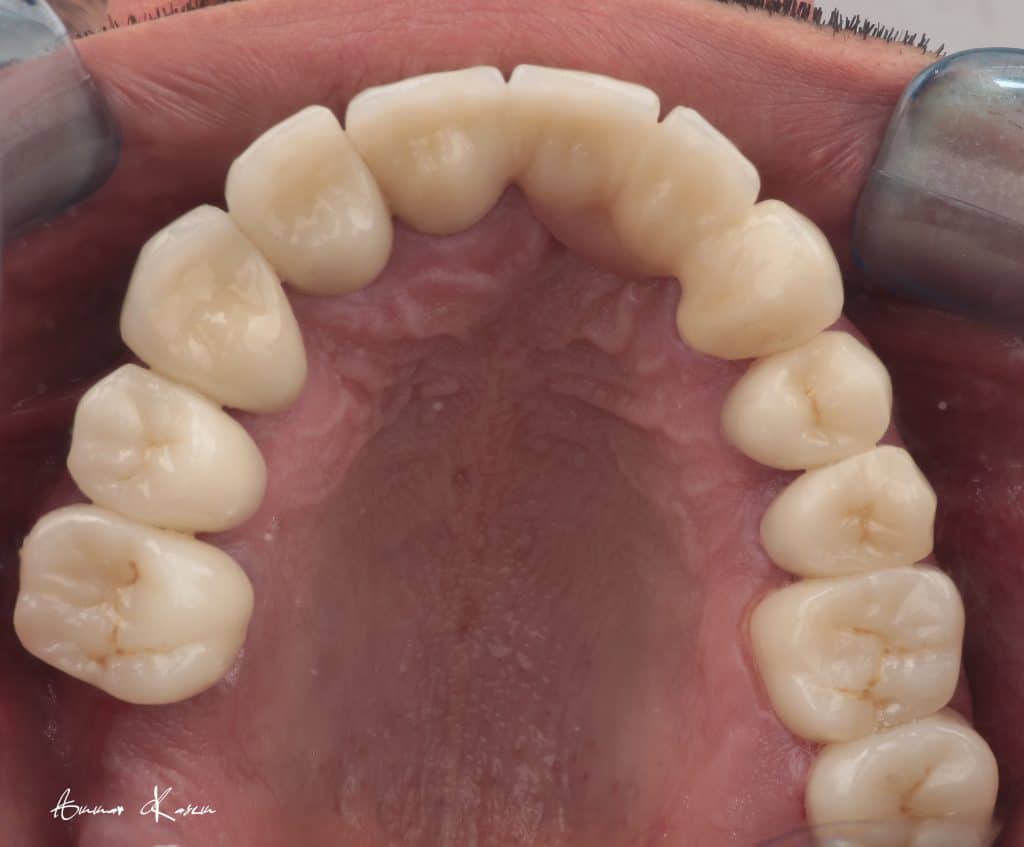

Temporization phase including;

5- 1st mock up ( edge to edge ) for 2 months

6- 2nd mock up ( Normal class I) for 3 months

7- Preparation phase through half arch technique to preserve the vertical dimension

8- Ceramic fabrication including zirconia bridge and e.max crowns